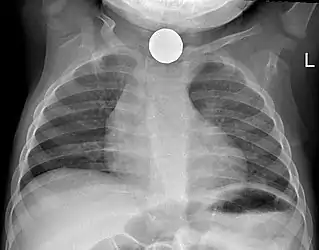

Commonly swallowed objects include coins, buttons, batteries, and small bones (such as fish bones),[1] but can include more complex objects, such as eyeglasses,[5] spoons,[6] and toothbrushes[5] (see image).

Prior to undertaking endoscopy, attempts should be made to locate the foreign body with x-rays or other non-invasive techniques.[1] For radio-opaque objects, x-rays of the neck, chest and abdomen can be used to locate the foreign body and assist endoscopy.[9] Alternative approaches, including the use of metal detectors, have also been described.[10]

X-rays are also useful for identifying the type of foreign body ingested and complications of foreign body ingestion, including mediastinitis and perforation of the esophagus.[1]